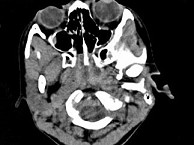

4.女,8歲,頭痛,鼻塞半年余,CT如圖所示,最可能診斷為  (    )

正確答案:C